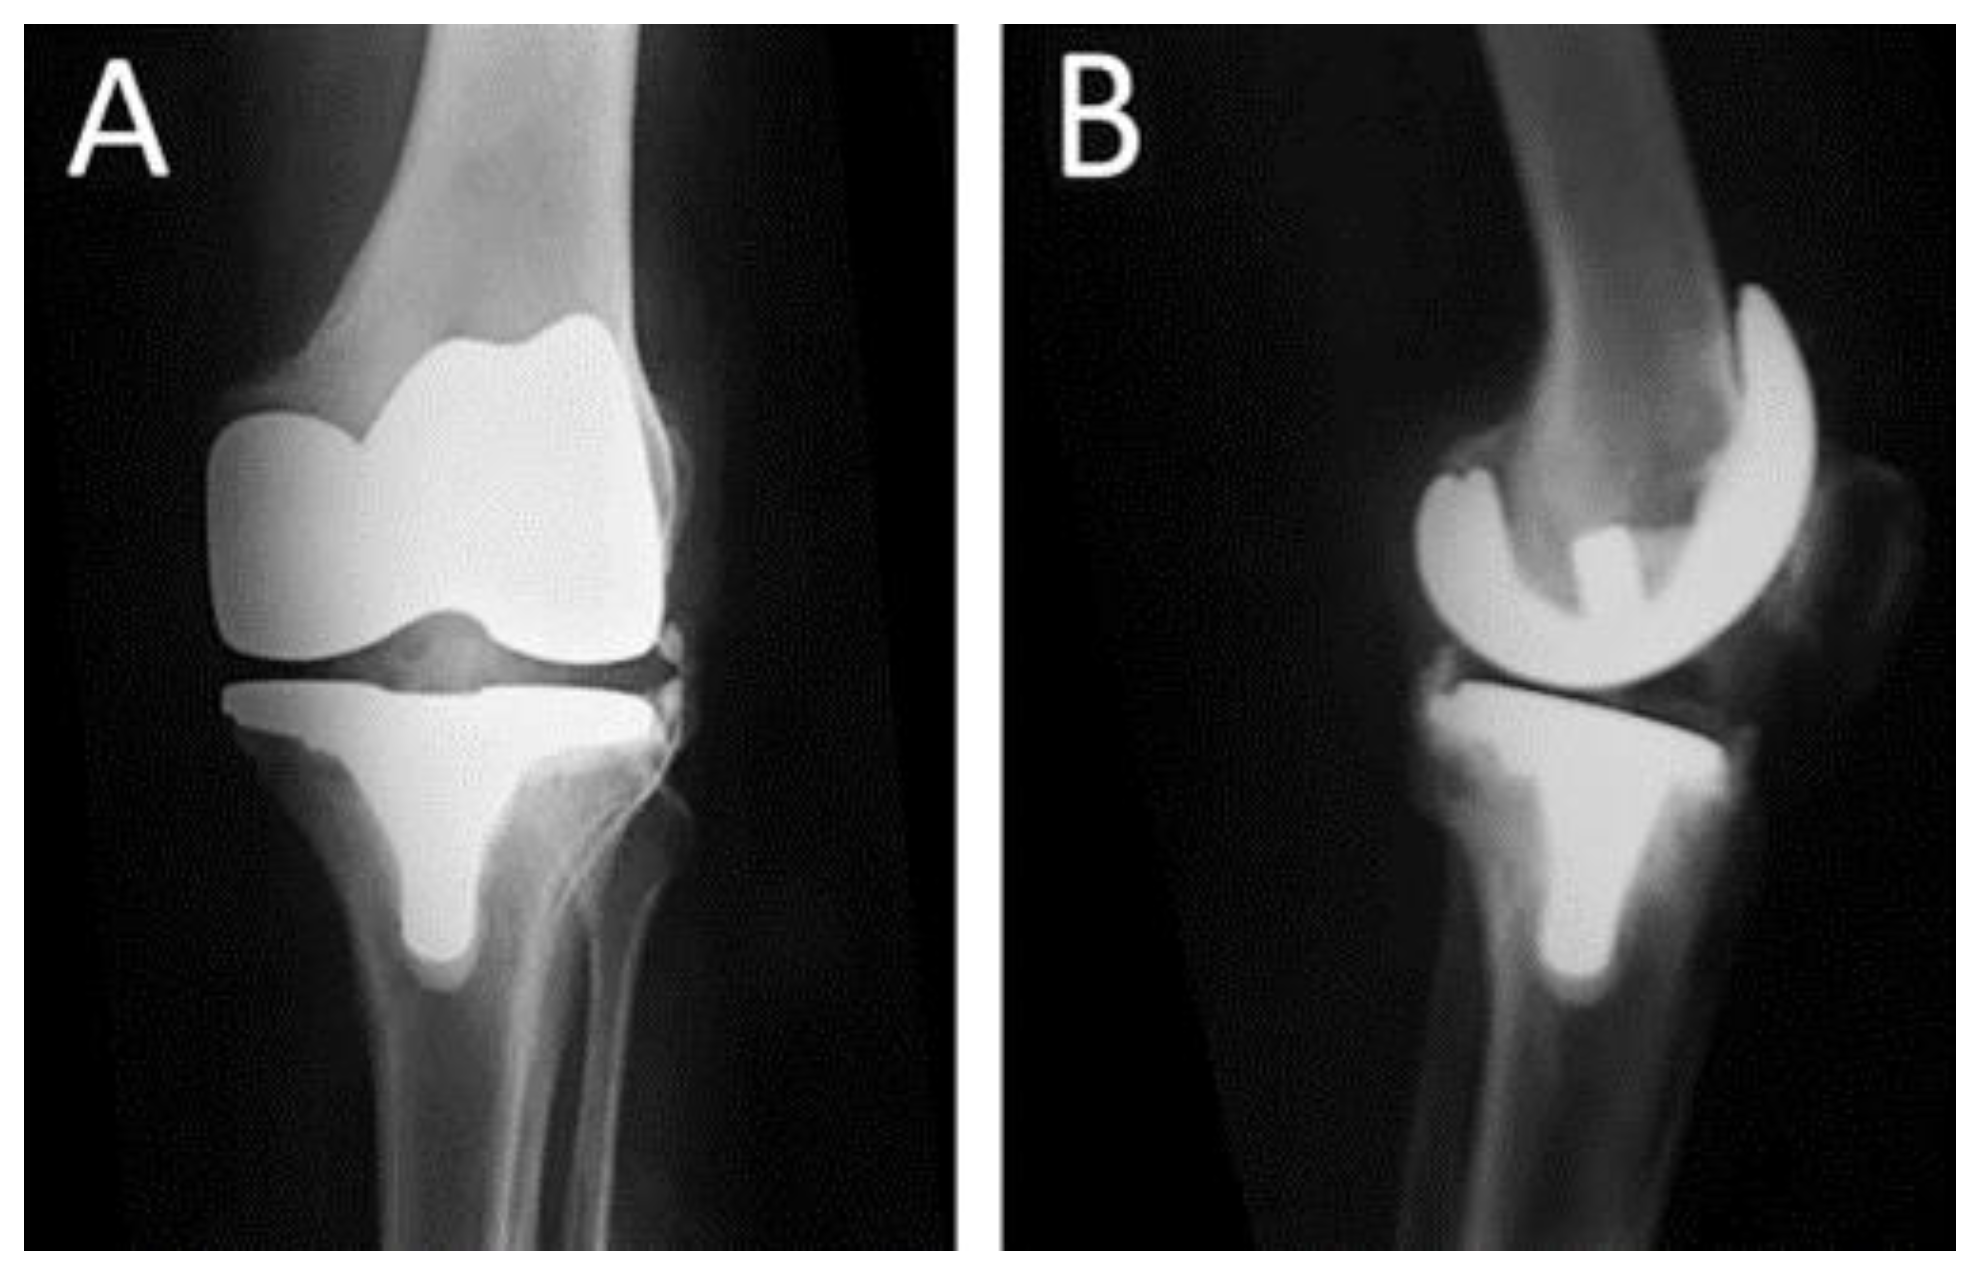

The clinical records and imaging studies of 8 consecutive patients with persistent PJI after two-stage revision for infected TKA that underwent knee arthrodesis with a silver-coated modular knee prosthesis (MUTARS®®- Munster Arthrodesis Implant cast GmbH, Buxtehude, Germany) between 2016 and 2022 in our department were retrospectively reviewed. Primary osteoarthritis was the indication for primary TKA in all patients (Figure 1 and Figure 2).

Figure 1.

Postoperative radiographs of a 67-year-old female who underwent total knee replacement due to osteoarthritis of the left knee (A) Anteroposterior and (B). Lateral radiograph of the knee.